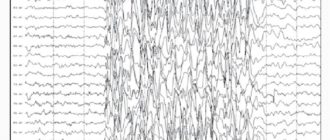

Электроэнцефалография при эпилепсии у детей | Малыш здоров! ЭЭГ или электроэнцефалографическое исследование – это

Эпилепсия: причины возникновения у взрослых и детей Современная медицина относит к эпилепсии патологии центральной